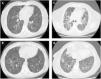

She was referred to our outpatient clinic complaining of fatigue and progressive dyspnea with moderate exertion in the previous year. Chest HRCT showed bilateral multiple cysts predominantly in the pulmonary inferior lobes (Fig. 1A,B), some traction bronchiectasis and limited areas of emphysema and mosaic attenuation. Serum specific IgGs were positive for parakeets and pigeons. Complete autoimmune study and VEGF-D were normal. Pulmonary function tests revealed FVC 89,9% and a severe-moderate decrease in DLCO (DLCO 49,4%, KCO of 57,3%). Bronchoalveolar lavage with differential cell count showed 15% of lymphocytes. The nonspecific nature of these results combined with the possibility of other CLD, like lymphocytic interstitial pneumonia, prompted a request for a lung biopsy; the histological examination revealed a cellular interstitial pneumonitis with peribronchiolar pattern and microgranulomas compatible with HP.

Currently, the patient is clinically and functionally stable (FVC 84%, DLCO 55% and KCO 72%); although HRCT shows no changes regarding multiple cysts, there are extensive areas with mosaic attenuation associated with ground glass opacities, traction bronchiectasis and loss of lobar volume (Fig. 1C,D).